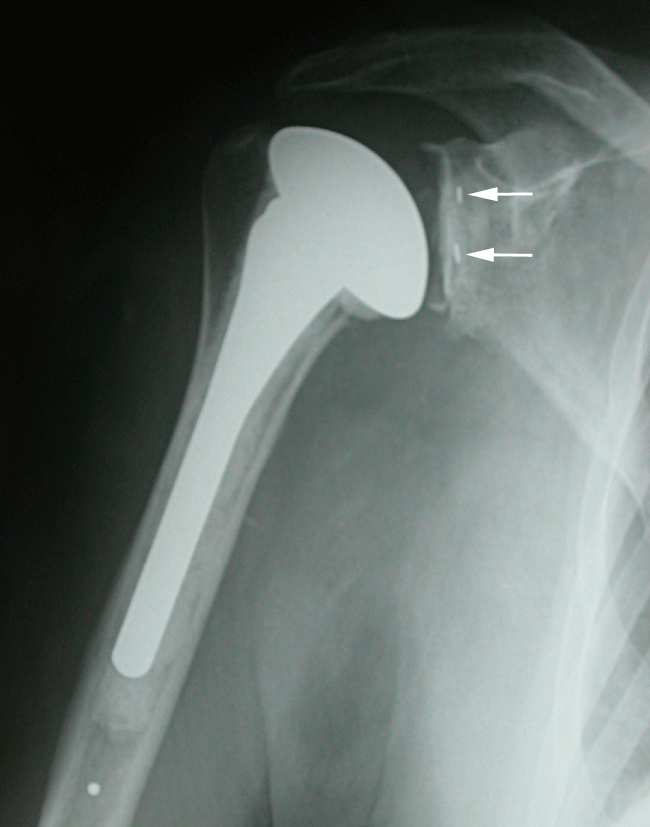

A long terme c’est la pièce glénoïdienne qui pose le plus de problèmes de descellement. Ces descellements se voient sur les radiographies sous forme de liseré évolutif entre la prothèse et le ciment ou entre le ciment et l’os.

Prothèse totale à 10 ans de recul.

Aucun liseré autour de la quille de la pièce glénoïdienne (flèches rouges).

Le liseré sous la surface articulaire n’a pas évolué depuis la pose (flèches vertes).

En cas de descellement ou d’usure, il est parfois nécessaire de réopérer pour sceller une nouvelle pièce glénoïdienne.